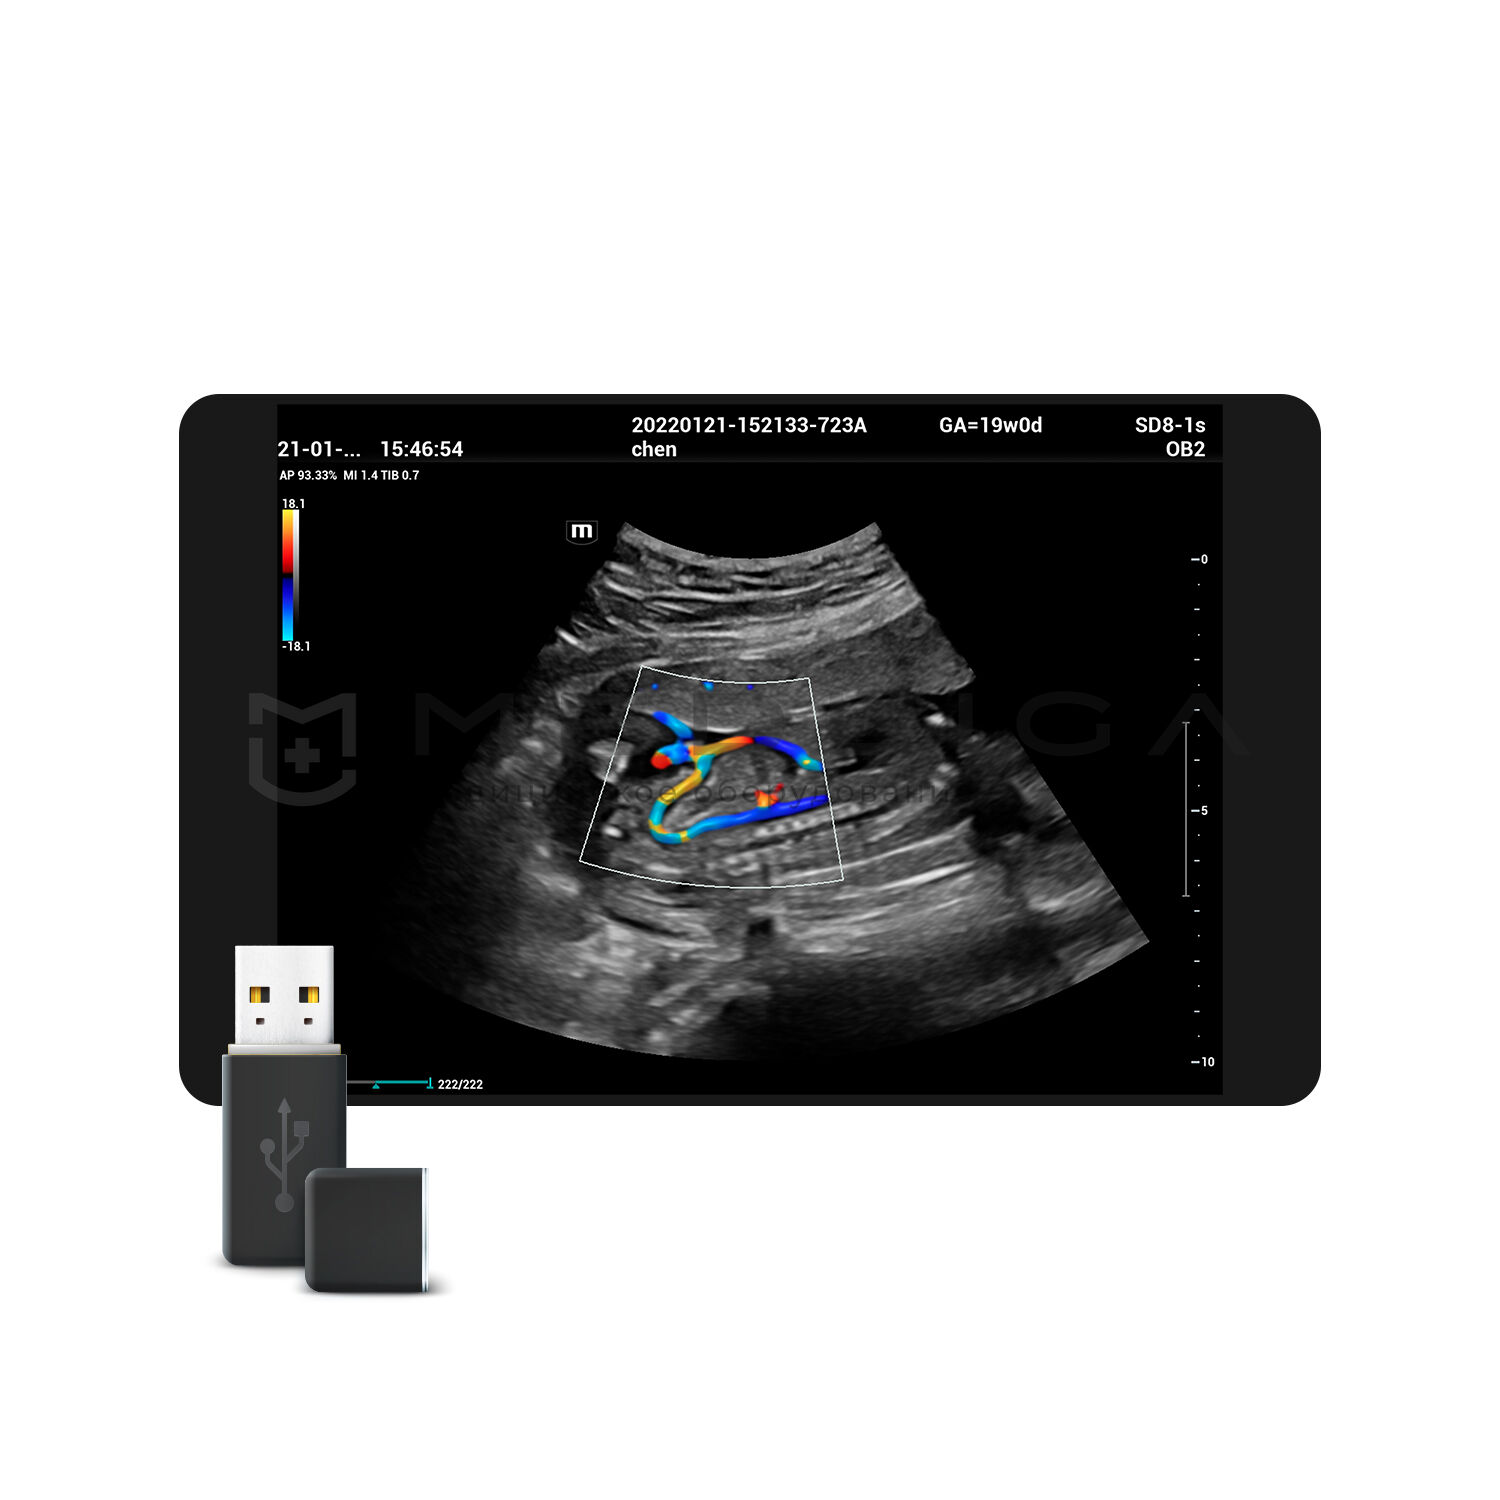

Области медицинского применения в основном определяются типом датчиков, работающих с ультразвуковым прибором и наличием специализированных режимов работы.

УЗИ аппараты общей визуализации предназначены для широкого спектра исследований, оперативной диагностики и повсеместно применяются в кабинетах ультразвуковой диагностики.

Для эхокардиографии используются секторные фазированные датчики и дополнительные допплеровские режимы с целью исследования сердечной деятельности.